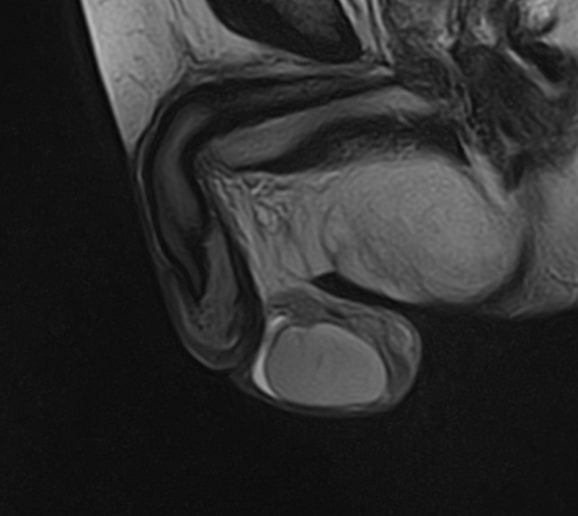

Магнитно-резонансная томография является одним из самых точных методов диагностики, основанный на использовании явления магнитного резонанса без применения вредного ионизирующего излучения, что имеет важное значение при обследовании органов репродуктивной системы.

Метод позволяет диагностировать патологию мужских половых желез (яичек), их придатков и семявыносящих протоков. Эти органы, вместе с кровеносными сосудами, лимфатическими протоками и нервами, располагаются в мошонке – мешотчатом образовании из гладких мышц и кожи.

Во время исследования производится послойное сканирование в трех взаимно перпендикулярных плоскостях с шагом от 1 мм, в дальнейшем с помощью инновационных приложений аппарат трансформирует полученные данные в трехмерные изображения. Методика позволяет выявлять структурные изменения органов мошонки на самой начальной стадии. Особенно это важно для диагностики опухолей.

При подозрении на развитие объемных образований, для проведения дифференциальной диагностики, может применяться контрастное усиление. В таких случаях, пациенту внутривенно вводится контрастный препарат, содержащий гадодиамид (соли металла гадолиния), который способен «высвечивать» патологические очаги при попадании в зону действия магнитного поля томографа. С помощью контрастирования удается выявлять опухоли размером от 1 мм. Ранняя диагностика онкозаболеваний позволяет вовремя назначить необходимое лечение.